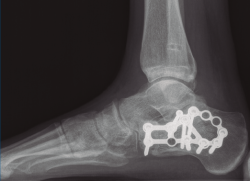

Figura 9. Control radiográfico posquirúrgico, anteroposterior.

Figura 10. Control radiográfico posquirúrgico, lateral.

Se dio de alta el día siguiente a la cirugía con un buen control analgésico. En la radiografía de control postoperatoria presentó una correcta reducción tanto de la fractura de calcáneo como de la articulación tibioperoneo astragalina (Figuras 9 y 10). Se citó en consultas externas 2 semanas después para la retirada de la sutura, presentado un buen aspecto las heridas quirúrgicas (Figura 11), y para la colocación de un botín de yeso. Dicho botín fue retirado al mes y medio de la cirugía, colocándose una ortesis estabilizadora de tipo Walker y autorizándose la carga parcial y progresiva, comenzando la rehabilitación.

A los 9 meses únicamente presentó dolor ocasional al nivel de la articulación subastragalina y molestias en la planta del pie al deambular descalzo, por lo que se pauta plantilla amortiguadora, con la que mejora notablemente la sintomatología. Presentó una puntuación de 83 sobre 100 en la escala de la American Orthopaedic Foot and Ankle Society (AOFAS), ligeramente superior a la media descrita en estudios previos(2,3). Radiográficamente se evidenció una anatomía restablecida del calcáneo y de la sindesmosis, así como una altura adecuada de ambos tobillos (Figuras 12 y 13). Dada la buena evolución, se decidió continuar con el seguimiento anual del paciente sin realizar la extracción del material de osteosíntesis, para valorar la necesidad de una futura artrodesis subastragalina.

Figura 12. Radiografía de perfil a los 9 meses de la cirugía.

Figura 13. Radiografía anteroposterior de ambos tobillos a los 9 meses de la cirugía.